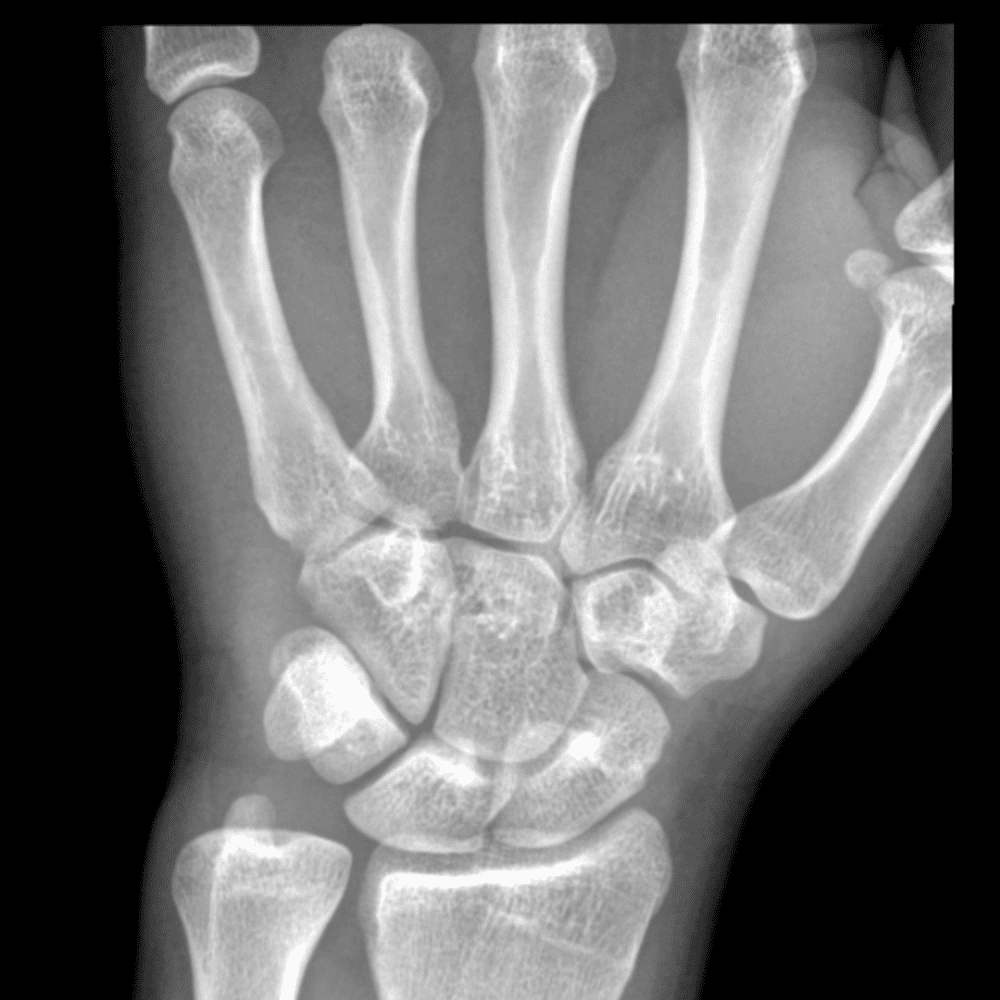

Simuliert den Dienst durch subtile oder schwierige Fälle und einige Normalbefunde.

30 Fälle